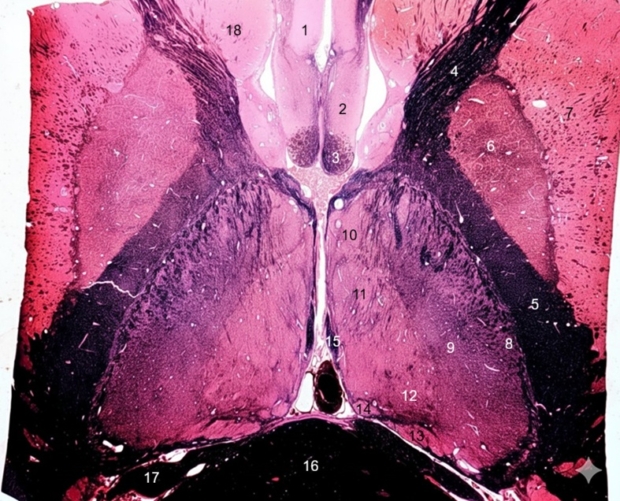

1. Subcallosal area

2. Paraterminal gyrus

3. Column of fornix

4. Anterior limb of internal capsule

5. Posterior limb of internal capsule

6. Globus pallidus

7. Putamen

8. Reticular nucleus of thalamus and external medullary lamina

9. Ventral thalamic nuclei: VA, VL, VP